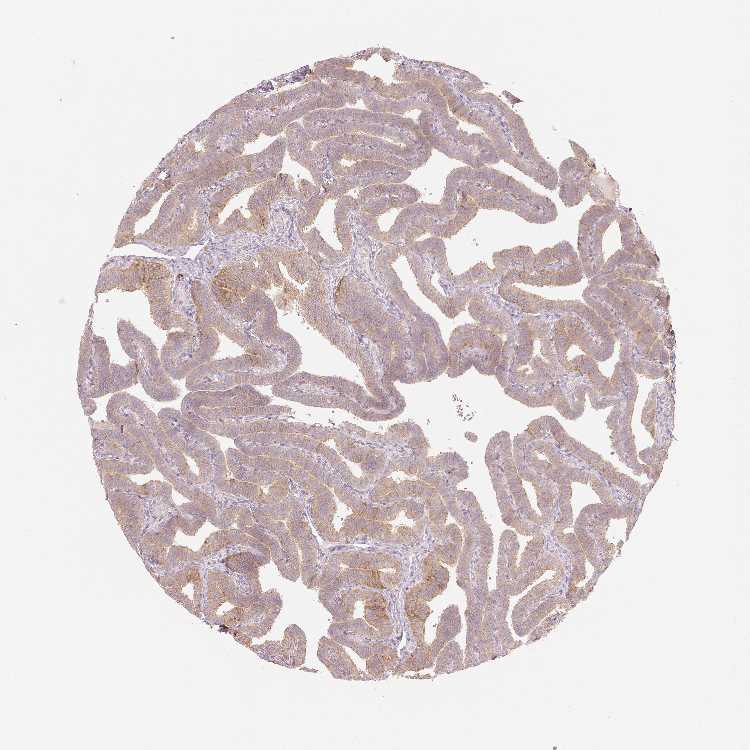

OR13C3